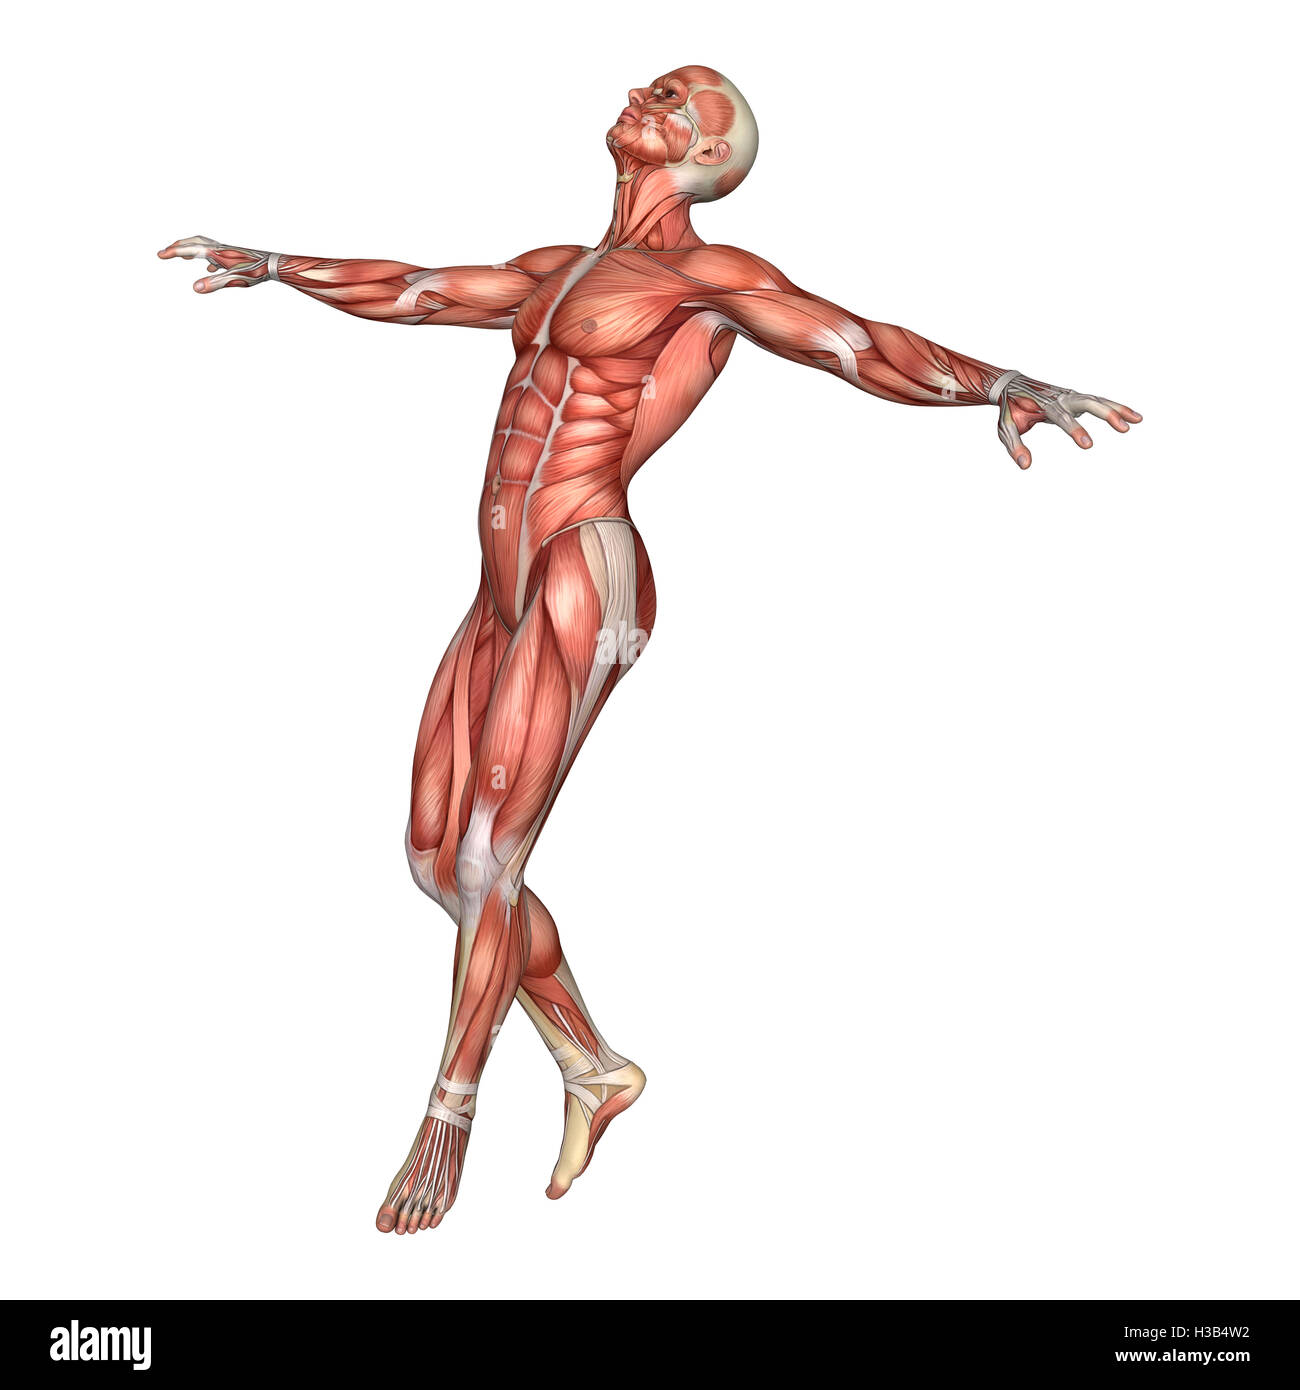

RFH3B4W2–3D-Rendering einer männlichen Anatomie-Figur mit Muskeln Karte isolierten auf weißen Hintergrund